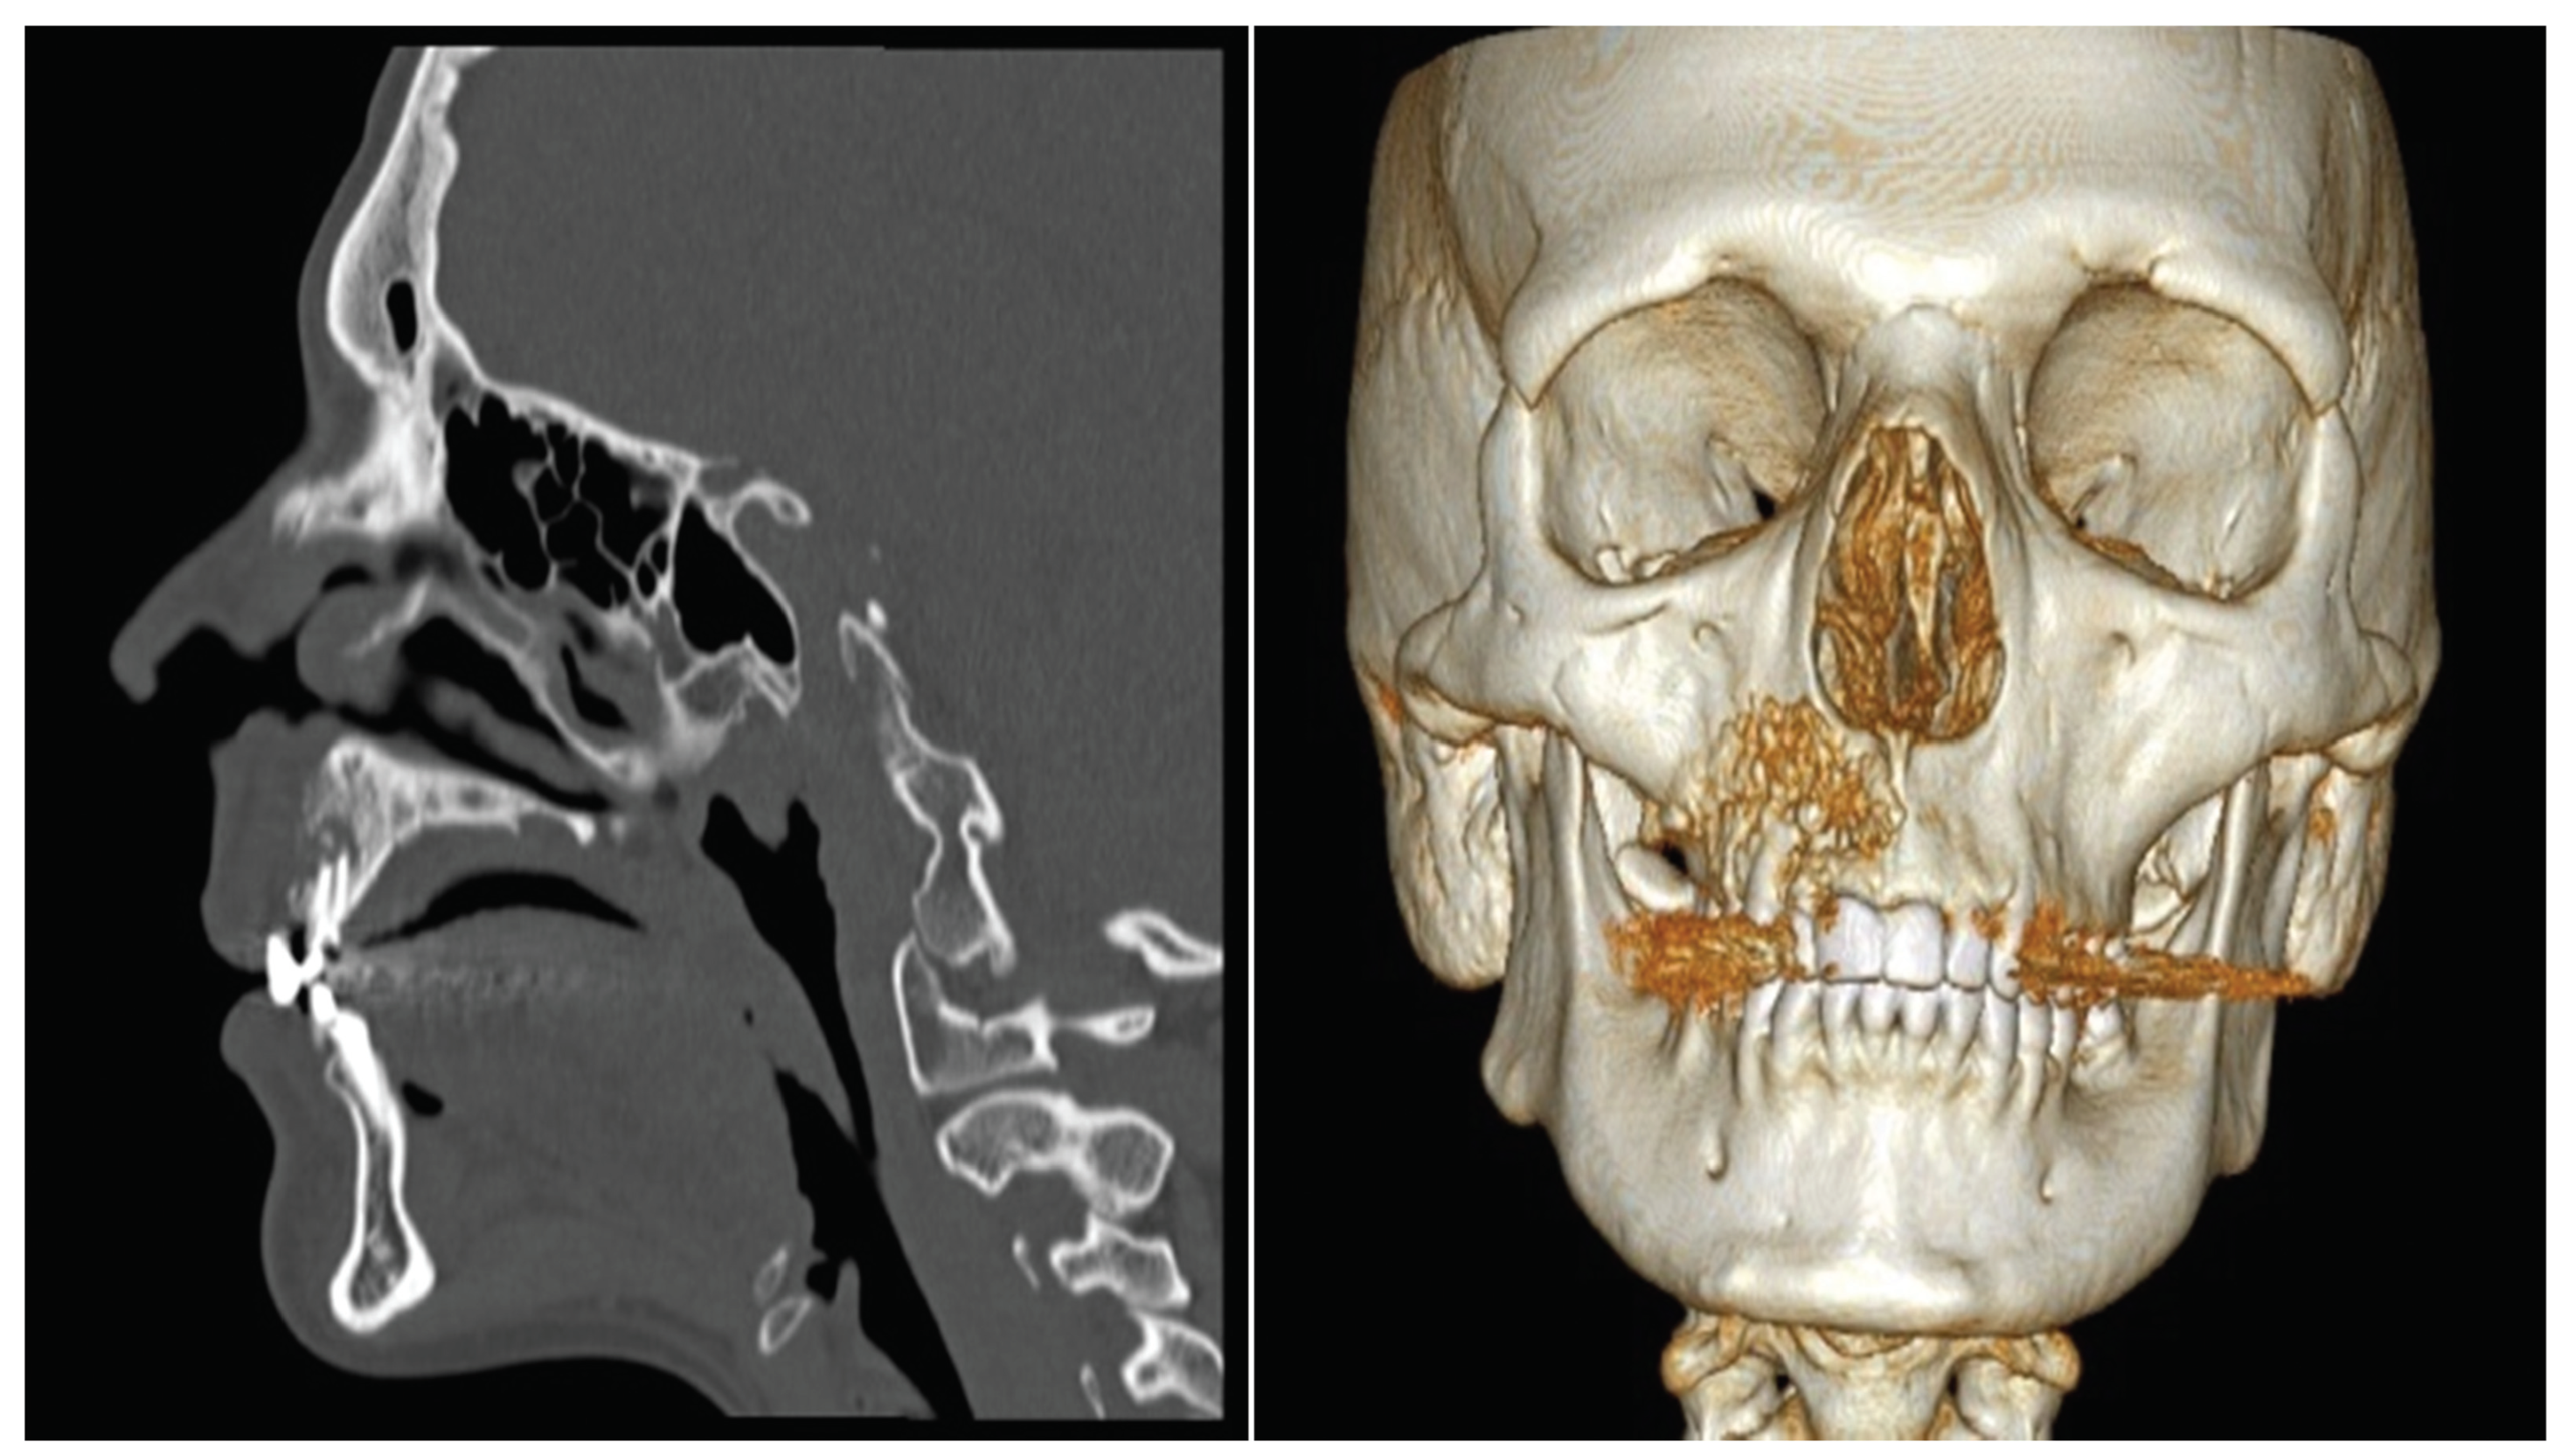

Surgical planning included virtual planning (Figure 1) based on 3D CT scan data (1 mm resolution) and imported into a CAD file. Thus, simulation of the surgical procedure with a 3D bio model (Figure 2c), produced by SL technique, allowed better visualization of the skeletal structures and the generation of custom-made surgical guides to better restore facial symmetry.

Figure 1. Virtual planning using 3D reconstruction software (Anatomics Pro, Anatomics TM, Melbourne, Australia) based on 3D CT scan data.